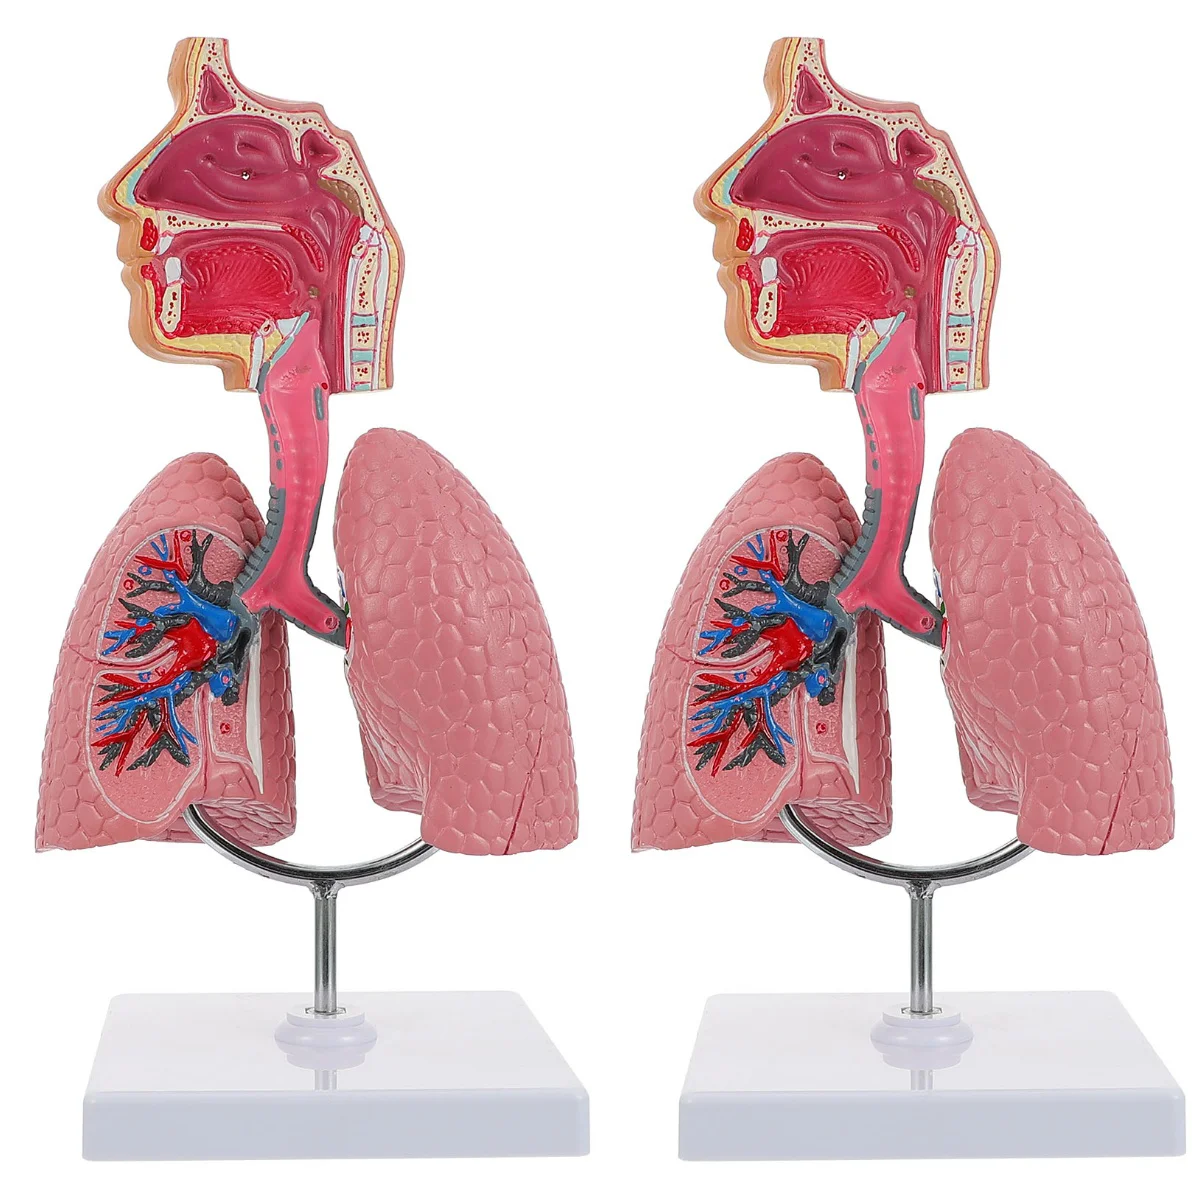

Лёгкие человека: Учебные картинки для детей